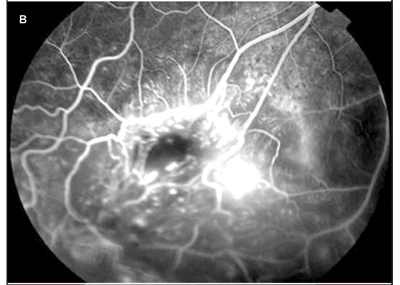

A angiofluresceinografia evidenciou enchimento precoce na fase arterial (Figura 2A) e, no decorrer do exame, extravasamento de contraste pelos vasos incompetentes (Figura 2B) com hiperfluorescência tardia em toda lesão (Figura 2C). Não foram detectadas áreas de exclusão capilar. Foi observada também hiperfluorescência na região foveal, que aumentou durante o exame no OD (Figura 3). Não foi demonstrada qualquer alteração no OE.